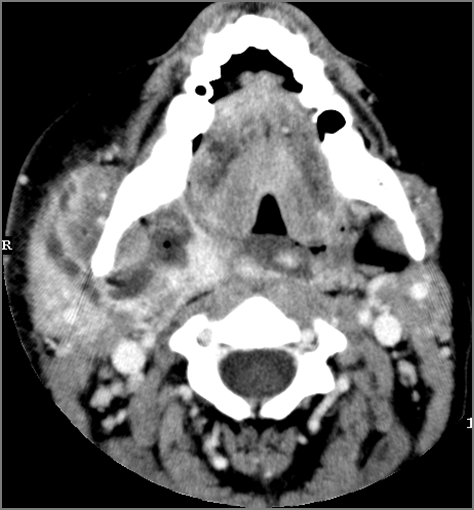

Oral Cavity, Floor of the Mouth, Maxilla and Mandible

There is edema/abscess within or surrounding the buccal space, masticator space, floor of the mouth, submandibular space or the adjacent superficial fascia or subcutaneous fat and skin. [Yes/No]

Major Salivary Glands

The parotid, submandibular and sublingual glands are enlarged. [Yes/No]

The parotid, submandibular and sublingual glands do show abnormal enhancement. [Yes/No]